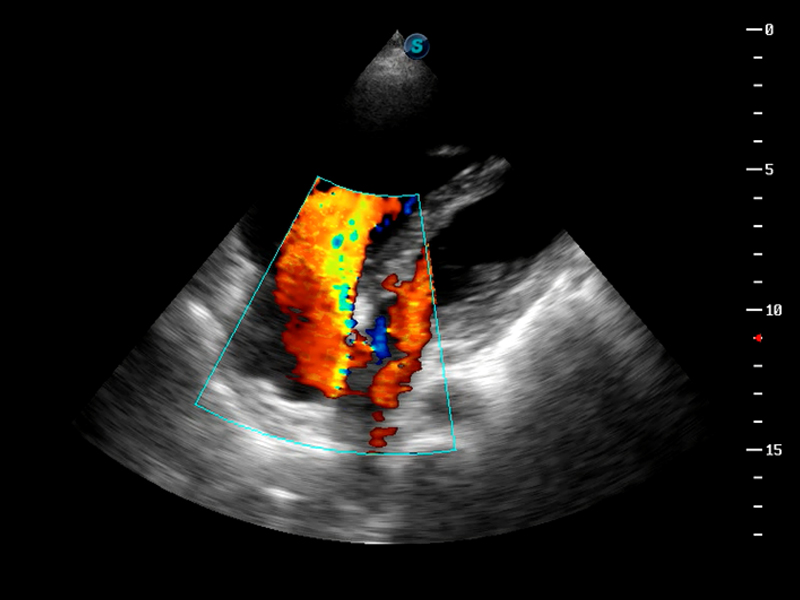

S9便携式彩色多普勒超声诊断仪是环球UG官网研发的高端便携彩超设备,外观设计新颖、产品性能卓越。S9在便携超声领域采用了突破传统的触摸屏交互设计,并以先进的软件硬件技术和设计理念,为您带来清晰的图像质量、稳定的工作性能和便捷的操作体验。

TDI组织多普勒成像

AutoC智能血流追踪